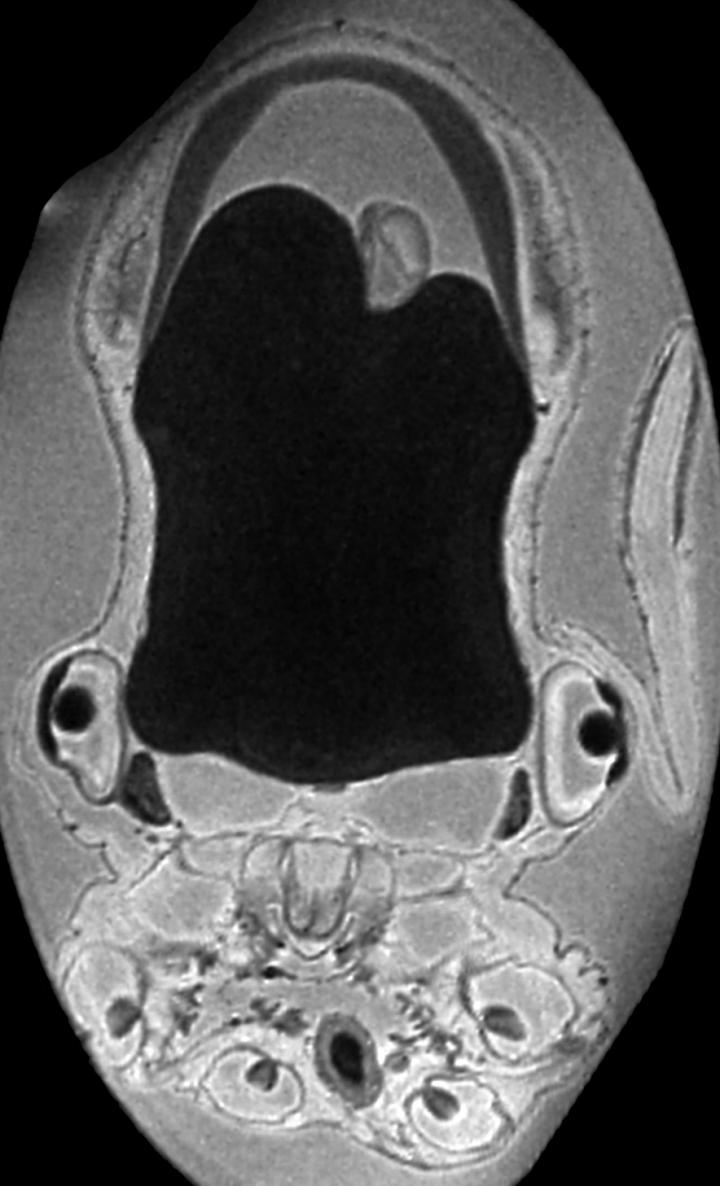

To find out more about this rare specimen, the team of Prof. Cornelius Faber at the University Hospital Münster took a look inside using a high-resolution magnetic resonance scanner. Dr. Ziegler then used the MRI images to create an interactive three-dimensional model of the internal organs of the small deep-sea octopus. “Particularly striking was a large yolk sac, which serves as a nutrient source directly after hatching, until the young animal can independently capture its prey in the deep sea”, explains Dr. Ziegler.

The scientists were surprised how much the structure of other internal organs and of the nervous system resembled that of adult animals. “While the octopuses we know from shallow waters usually care for their brood, such behavior does not seem to impart any evolutionary advantage to deep-sea dumbo octopuses”, Dr. Ziegler explains.

nervous system yellow, intestinal tract blue,

shell red, fin cartilage pink, gills and branchial

glands green, statocysts purple.

Credit: © Alexander Ziegler